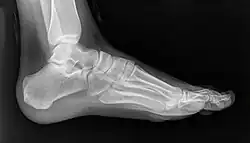

Zdjęcie stopy